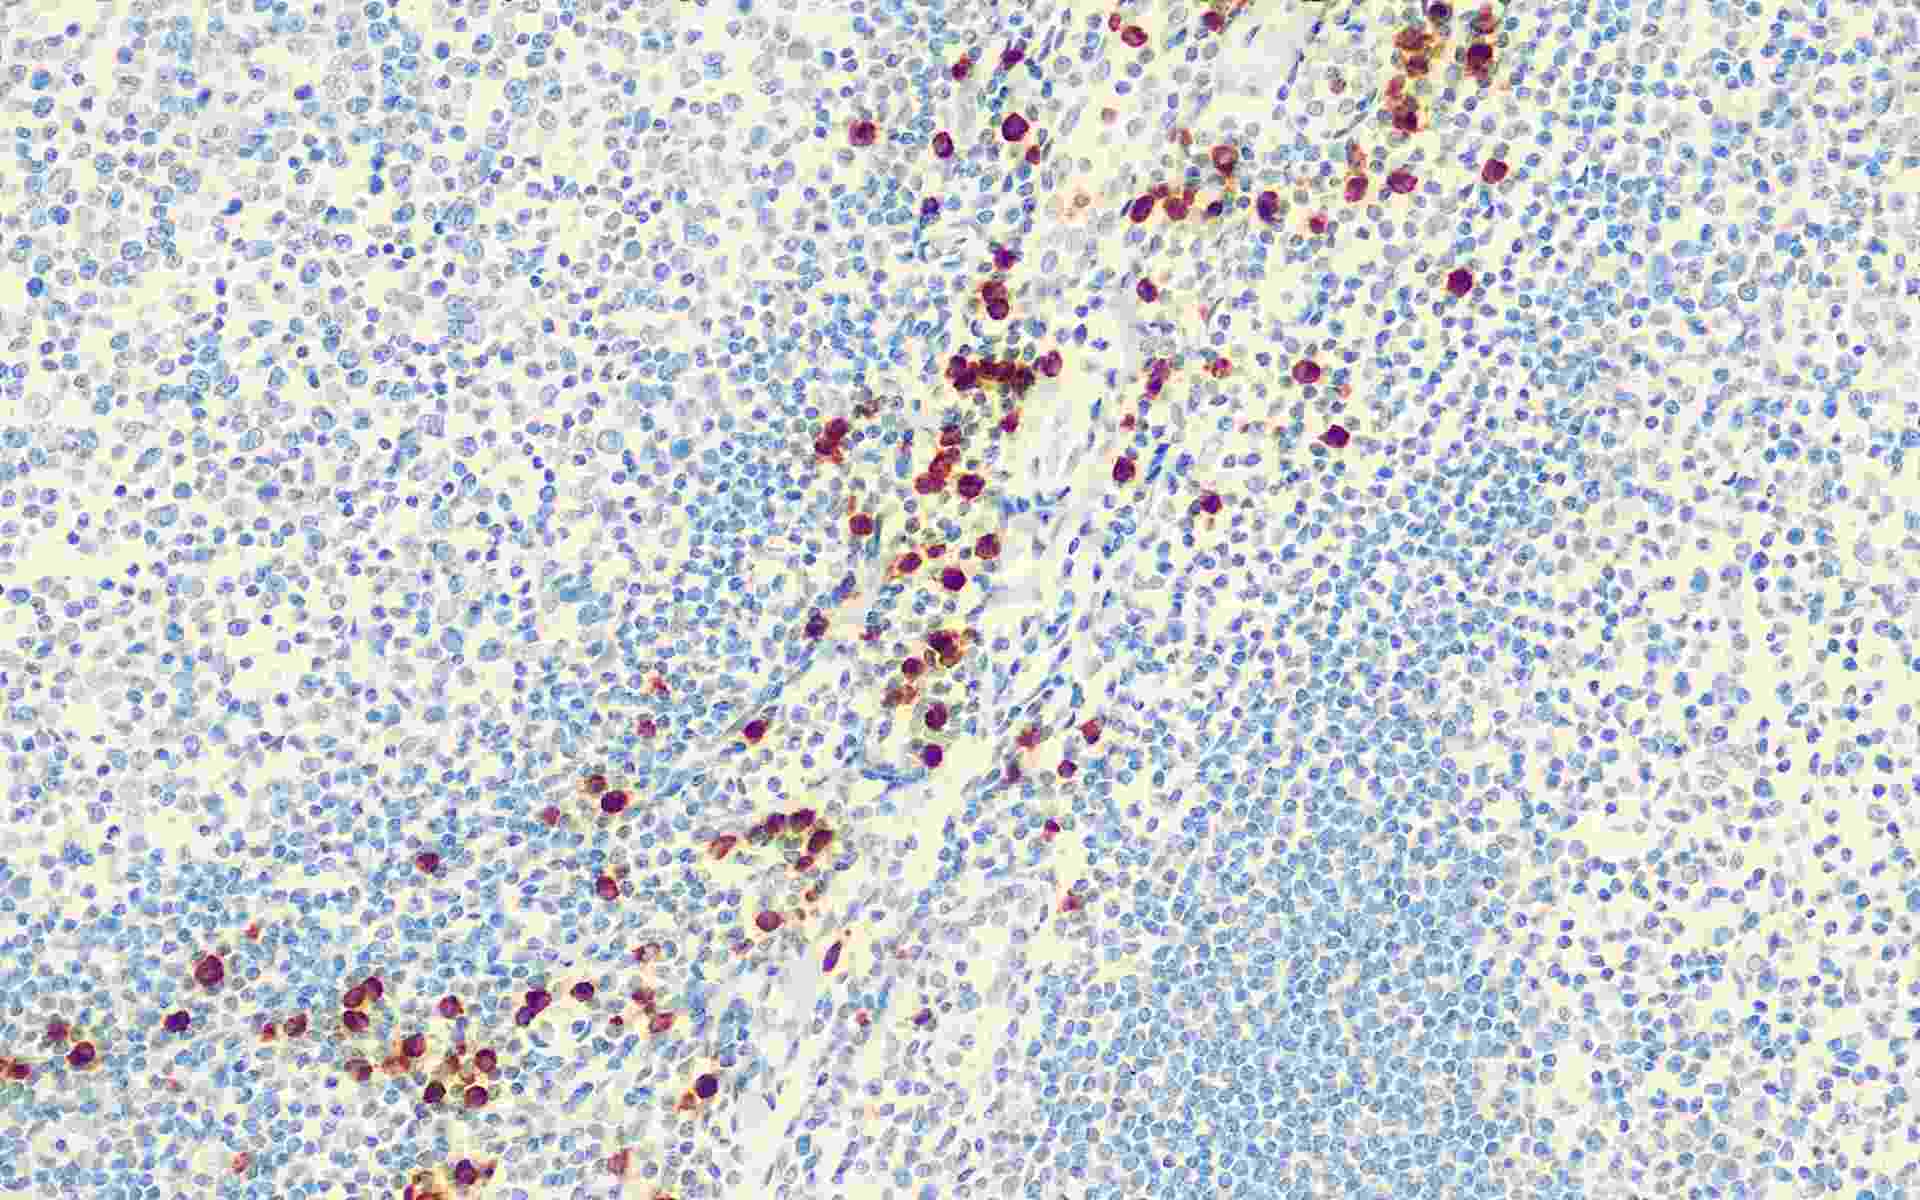

Granzyme B

Granzyme B是一种分子量为29kDa的中性丝氨酸蛋白酶,存在于特异性的细胞毒性T细胞和自然杀伤细胞中。主要用于研究肿瘤组织中细胞毒性T细胞。可用于自然杀伤细胞、T细胞淋巴瘤以及退行性大细胞淋巴瘤的研究。此外,高比例的细胞毒性T细胞可用于何杰金病不良预后的研究。

• GRB扁桃体